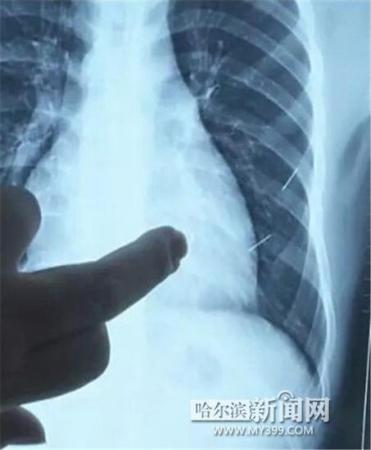

醫生指出X光片上的針狀物

昨日上午,記者在哈醫大二院第八住院部心外三病房找到了躺在病床上痛苦不堪的董立仁,家屬正在他身旁不斷安慰著他。見記者前來,董立仁母親李百燕拿出一張X光片,上面可以清晰地看到胸腔內一共有4根針狀物,其中一根在心臟部位,兩根在胸腔壁上,還有一根在腹腔壁上。